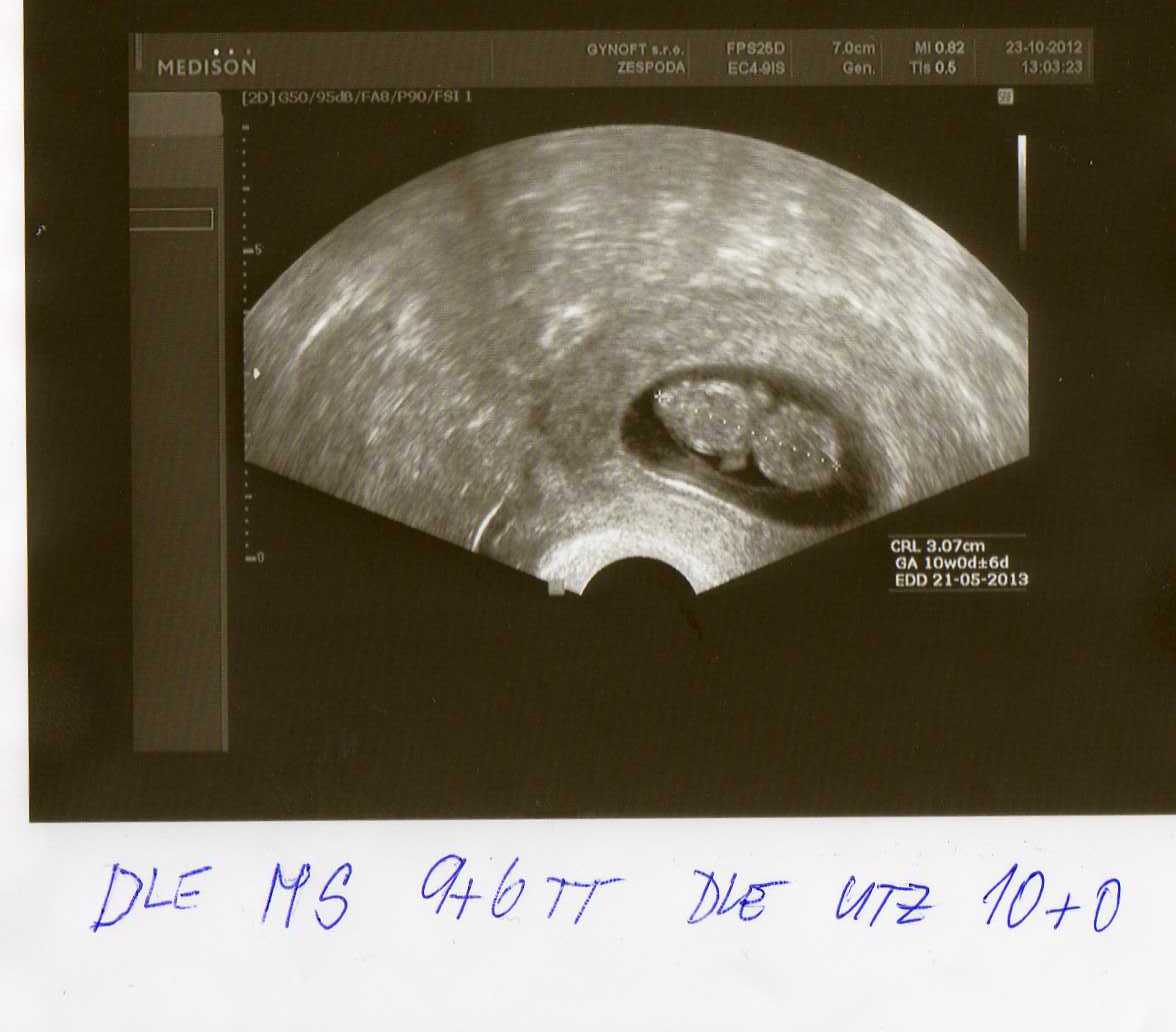

Ahojky holky moje,tak jsem zpět 😉 UF.....brouček krásně vyrostl a i se hýbal 😉 má 3,07cm a odpovídá na 10+0tt takže má 1den náskok 😉 .Jsem objednaná na příští čtvrtek na odběry a vystavení průkazky,byl mi nabídnut screening,který dělají ve Slaném a stojí 900kč...tak holky nevím...já bych do toho šla ale uvidíme co na to manžel 😉